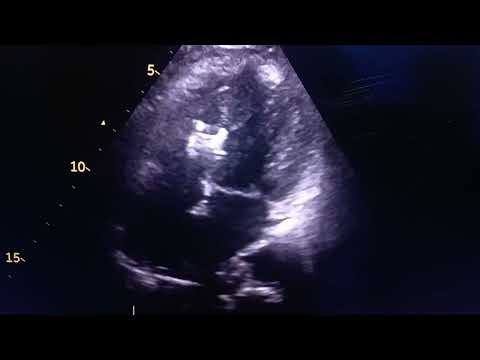

Preparing for a Cardiac Catheteriz…